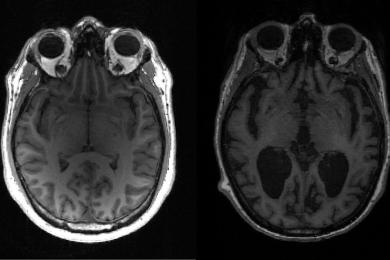

ألزهايمر